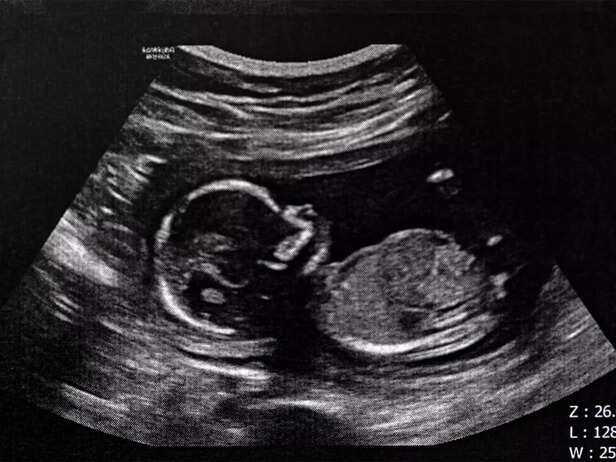

baby fetus

In case of abnormalities, additional tests or consultations may be necessary.